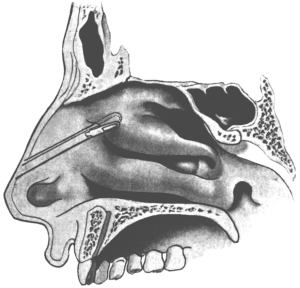

| 345. | Catheterizing the Sphenoidal Sinus | 654 |

| 346. | Killian’s Long Nasal Speculum | 655 |